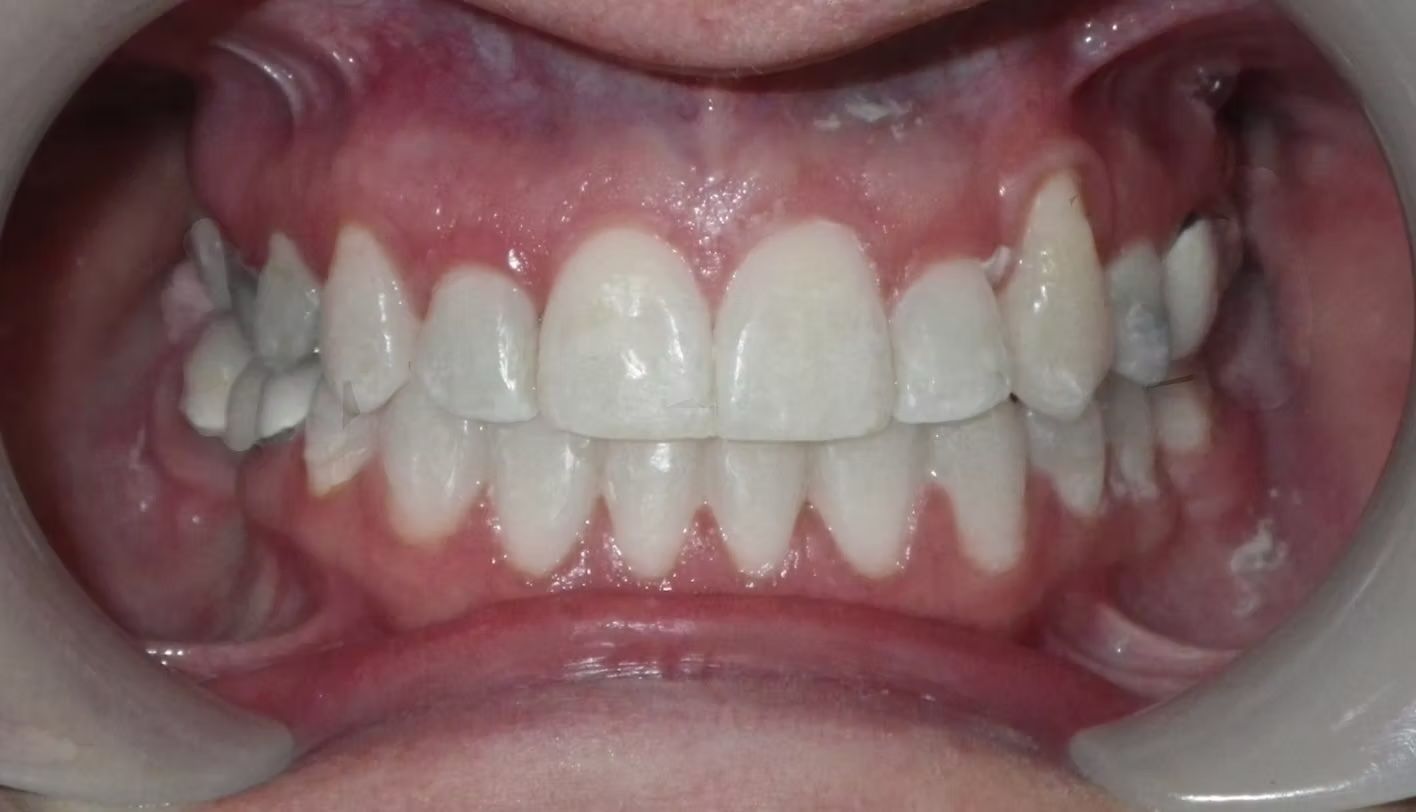

AMBER

Amber, began treatment with Dr. Bret because she didn't like that her front teeth overlapped each other. She had narrow top and bottom dental arches with severe crowding of her upper and lower teeth. She was treated with braces on the upper and lower teeth, and we used the braces to widen the smile. What a change!